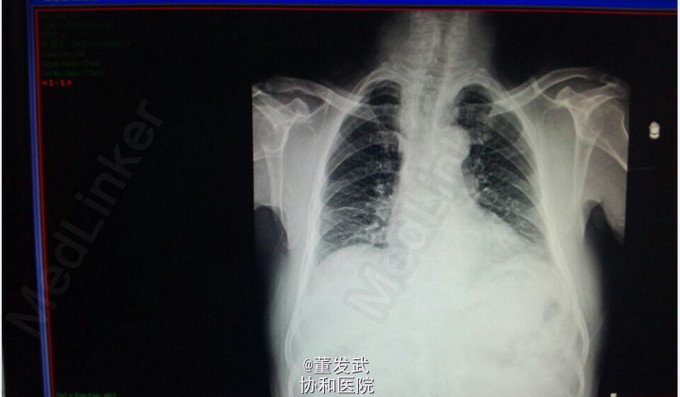

患者男,31岁。主诉:间断胸闷气促3年,加重1天。现病史:患者于3年前无明显诱因出现活动后胸闷、气促,于我院诊断为“致密化不全心肌病 二尖瓣关闭不全 左心扩大“,治疗好转后出院,此后规律随访,无特殊不适。于2015.04.01日-04.12日(2月前)再次因胸闷气促加重来我院就诊,病情好转后出院。患者于昨日开始无明显诱因上述症状再次出现,感气促、胸闷,时有干呕,伴心悸、乏力、纳差,来我院途中持续性发作胸口正中处疼痛约20分钟,未服药逐渐缓解,无发热、咳嗽咳痰、黑朦、晕厥、肢体水肿等异常。自起病以来,患者精神、饮食、睡眠欠佳,小便量一般,大便如常,体重未见明显改变,活动耐力明显下降。既往有心律失常发作、乙肝病史4余年,余无特殊。

查体:生命体征平稳,神清,唇红,颈静脉无充盈,心音低钝,心尖部闻及收缩期吹风样杂音,双肺呼吸音稍粗,余查体无特殊。 辅助检查:胸部正位X线

初步诊断: 扩张型心肌病 全心增大 二尖瓣重度关闭不全 心功能Ⅲ级 处理 1、完善血、尿常规、肝肾功能、BNP等检查; 2、给予强心、利尿、抗凝、抗心肌重构等对症支持治疗; 3、密切观察病情变化,根据病情及时处理。